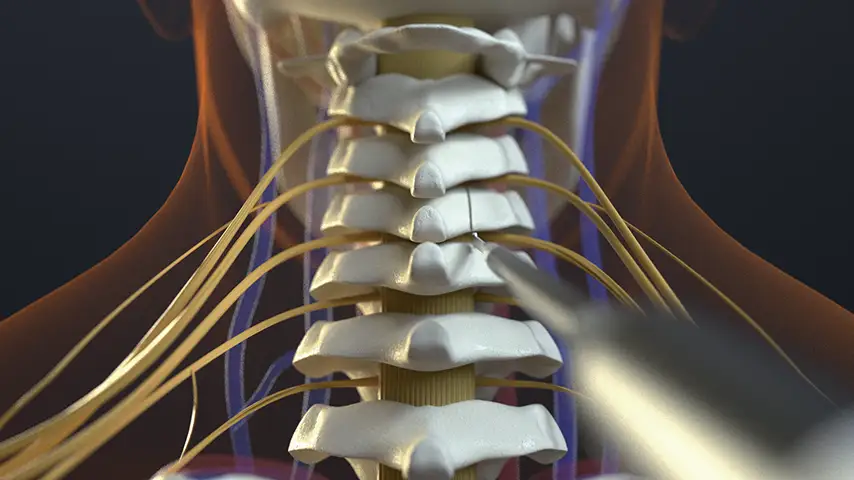

Selective osteotomies, safety on soft tissues

Laminotomy and Laminectomy

Selective cut preserves soft tissue. (Dura, neves and vessels)

CAVITATION EFFECT

Maximum intra-operative visibility.

Blood-free surgical site.